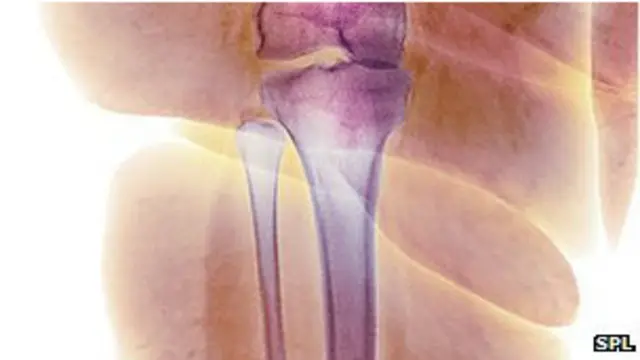

چاغښت د هډوکو د ناروغۍ سبب کېدای شي

له یوې نوې څېړنې وروسته ویل شوي، چې چاغتیا د هډوکو د یو ډول ناورغۍ " آسټیوپوروسس " سبب کېدای شي چې په کې هډوکې ناتوانه کېږي.

د امریکايي ساینسپوهانو په څېړنه کې معلومه شوه، چې د ځینو چاغو کسانو په هډوکو کې غوړ پټ وي، چې له کبله یې هډوکې کمزوري کېږي او په اسانۍ ماتېدای شي.

څېړنې ښودلې، چې د چاغو کسانو د بدن په بېلو برخو لکه ځیګر، پلې او هډوکو په مغز کې غوړ پټ وي. دغه څېړنه کې شامله ډاکټره مریم بریډیلا وايي هغه کسان چې بدن یې مڼې ته ورته وي، تر ټولو زیات له خطر سره مخامخ وي.

دا هغه کسان دي، چې ډېر وزن یې د ملا په شاوخوا کې ورټول وي. د هډوکو مغز هغه ځای دی، چې د نوي هډوکي حجرې په کې رامنځ ته کېږي.

هغه کسان چې له دغې ناروغۍ سره مخامخ کېږي، د هغو د هډوکو به مغز کې ډېر غوړ وموندل شول. ویل کېږي چې چاغښت خپله یوه ناروغي ده او اوس معلومه شوه، چې د نورو ناروغیو سبب هم ده.

د ډاکټر برېډلا په وینا که د هډوکي د مغز ځای ته غوړ ننوځي، نو هډوکي ورسره ناتوانه کېږي. د هغې په وینا که مو د ملا په تېر کې غوړ ننوتي وي، نو ګومان نه شي، چې دا به ډېر وخت کار وکړي. هغه وايي:

یو وخت داسې فکر کېده، چې چاغښت هډوکو ته د زیان اوښتو مخه نیسي، خو موږ معلومه کړه، چې دا فکر ناسم و. د څېړونکو په وینا بدن کې د غوړو ځای نه کنترولېږي، ځکه غوره همدا ده، چې باید ځان له چاغتیا وژغورل شي.

اټکل کېږي، چې برتانیا کې ۳۰ میلیونه کسان د آسټیوپوروسس په ناروغۍ اخته دي. د دې ناروغۍ ښکار کسان معمولاً ټيټ قد لري او ناتوانه وي.